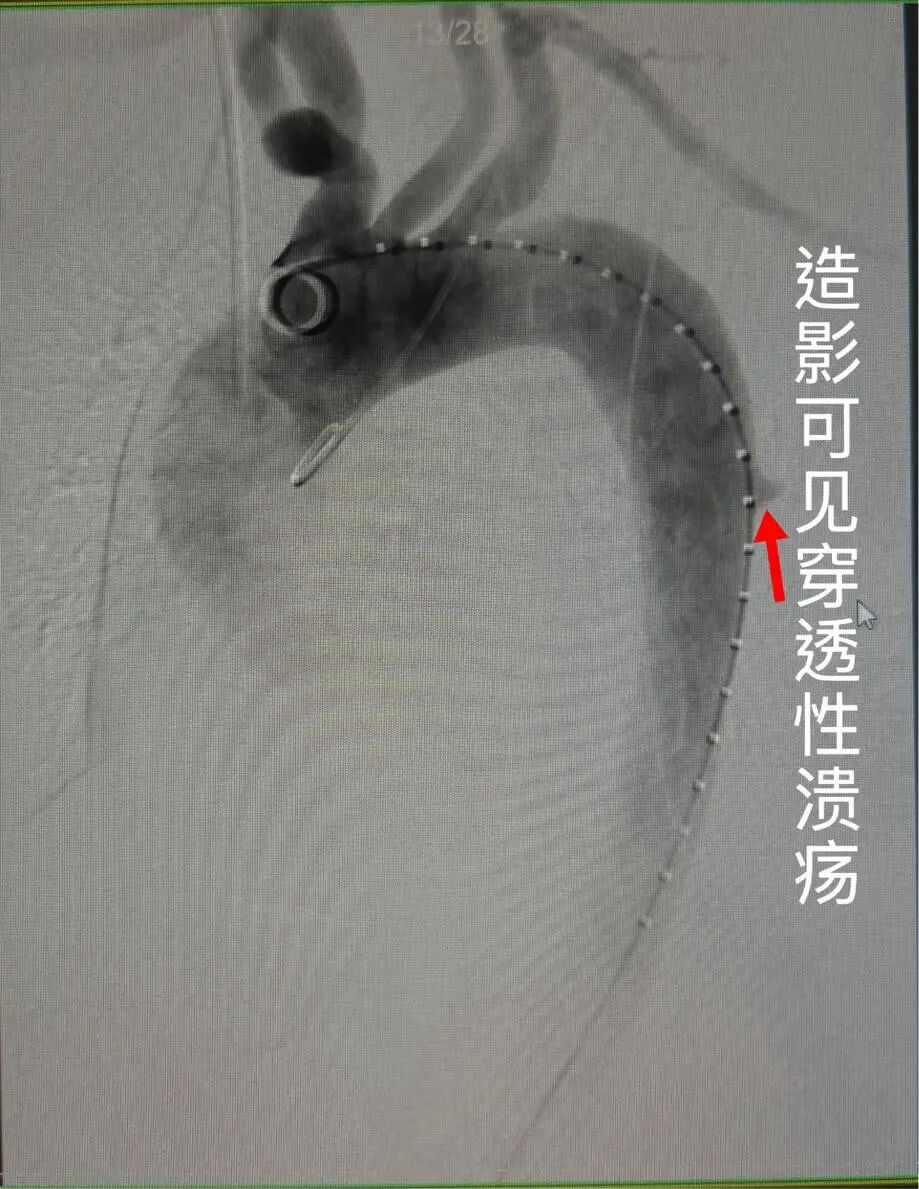

术前精准定位

图:术前主动脉造影(DSA),可见导丝、导管精准到位,清晰标记病变范围,为手术做好精准导航。